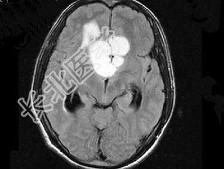

- 单项选择题男,32岁, 头痛,头昏半年, 加重10天伴抽搐,根据所提供图像, 最可能的诊断是 ( )

A、胶质瘤

B、颅咽管瘤

C、蛛网膜囊肿

D、表皮样囊肿

E、胆脂瘤